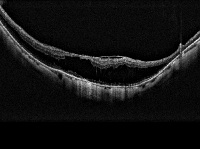

Для диагностики ретиношизиса используют базовые методы обследования: визиометрию, тонометрию, офтальмоскопию с использованием щелевой лампы и линзы Гольдмана. Для уточнения диагноза дополнительно назначают УЗИ глазного яблока, электроретинографию (для определения функционального состояния сетчатки), флюоресцентную ангиографию (для диагностики патологии в макуле, при врожденном ретиношизисе). Компьютерная периметрия помогает установить наличие дефектов в поле зрения. Оптическая когерентная томография является ведущим методом при данной патологии. Позволяет точно выявить изменения в макулярной области сетчатки, определить наличие кист и отслоек на периферии.